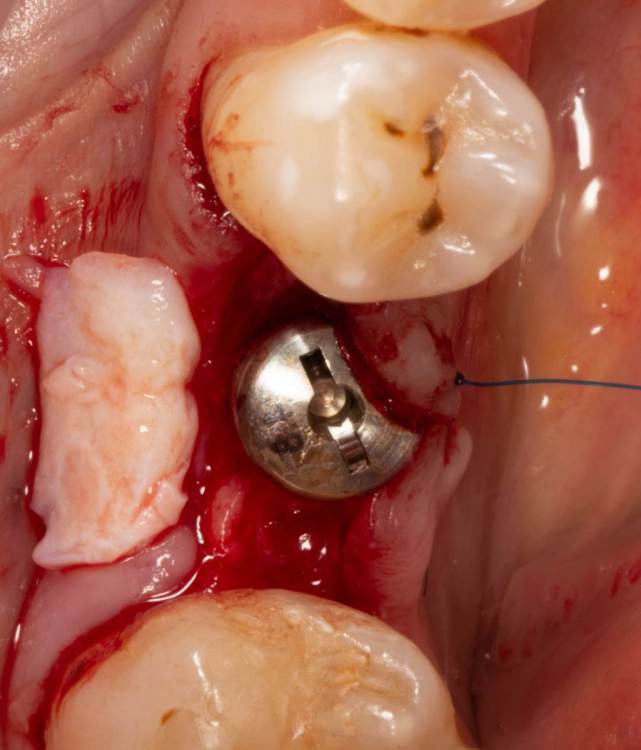

Женька Опубликовано 24 июня, 2023 Поделиться Опубликовано 24 июня, 2023 Собственно похожий случай. Разница лишь в том, что тут заглушка просвечивала. Предоп фоток, к сожалению, нет. 3.6*08мм, тк очень тонко было. Торк при установке потерял. Около 5 примерно был. В данном случае решил сст только вестибулярно положить. p.s. да, налёта много. Пациентка сестра моей одногруппницы, и чистит зубы только у сестры... при встрече я не думал, что чистки давно не было. Косяк, не отрицаю. Фотку со швами забыл сделать. Сделаем на снятии. Ссылка на комментарий

Женька Опубликовано 26 июня, 2023 Автор Поделиться Опубликовано 26 июня, 2023 @Fin корея. В отсутствии десны язычно. Кмк, эти проблемы я создал собственноручно. Неправильным разрезом и ушиванием, кмк опять же. @bakagaidzin в соседней теме про тл вообще сказали, что БЛ) и зачем так утопил Ссылка на комментарий

Женька Опубликовано 27 июня, 2023 Автор Поделиться Опубликовано 27 июня, 2023 Тут не стал сст сажать... тк при расщеплении язычно ниже платформы перфорировал лоскут( Подумал, что питания от перекинутого лоскута будет мало для сст. В первой теме-да, сст с двух сторон. Ссылка на комментарий

Irouil Опубликовано 27 июня, 2023 Поделиться Опубликовано 27 июня, 2023 @Женька а зачем расщепляете? 1 Ссылка на комментарий

Женька Опубликовано 27 июня, 2023 Автор Поделиться Опубликовано 27 июня, 2023 @Irouil создать место, куда сст вложить. Ссылка на комментарий

Irouil Опубликовано 27 июня, 2023 Поделиться Опубликовано 27 июня, 2023 @Женька это же язычная сторона, там же мобилизация относительно несложная полнослойно Ссылка на комментарий

Женька Опубликовано 27 июня, 2023 Автор Поделиться Опубликовано 27 июня, 2023 @Irouil ну, а руки то видимо всё ещё не из плеч) Там же получается идёт полированная шея имплантата, и видимо я завёл лезвие под неправильным углом. Ссылка на комментарий

Irouil Опубликовано 27 июня, 2023 Поделиться Опубликовано 27 июня, 2023 1 час назад, Женька сказал: @Irouil ну, а руки то видимо всё ещё не из плеч) Там же получается идёт полированная шея имплантата, и видимо я завёл лезвие под неправильным углом. Нет, расщеплять там любым рукам сложно, а вот полнослойно должно быть наоборот - элементарно, Урбан все подробно описал, надо лишь подавить аккуратно на лоскут Ссылка на комментарий